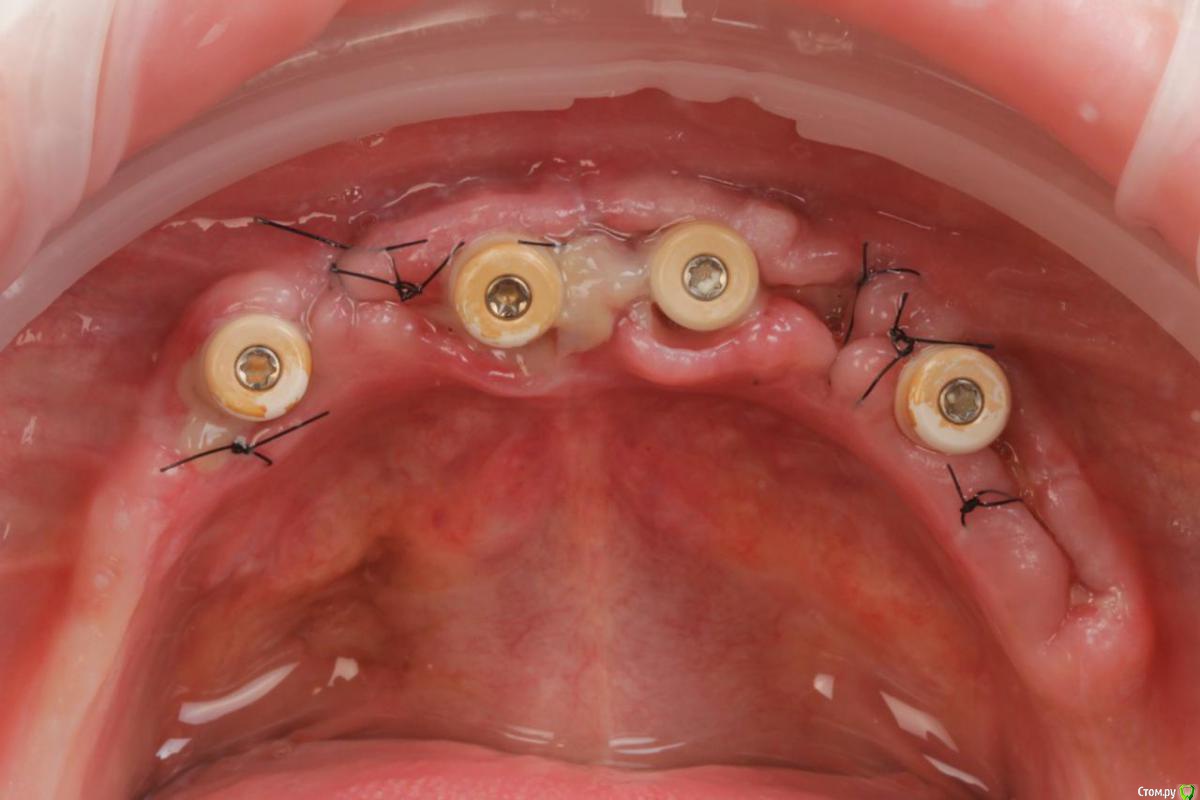

Bier Опубликовано 10 февраля, 2020 Поделиться Опубликовано 10 февраля, 2020 Хирургия в седации 3,5 часа + редукция гребня. По шаблону под пилот. Все мультиюниты были заранее выбраны техником и четко сели.Временные армированные протезы (лазерное спекание) 8 Ссылка на комментарий

Дмитрий Л. Опубликовано 10 февраля, 2020 Поделиться Опубликовано 10 февраля, 2020 Ого, ну и высота!Сразу бросаются в глаза нижние дистальные мультиюниты. Зачем было располагать имплантат с дистальным наклоном, чтоб потом техник развернул мультиюнит мезиально? Уже можно было вертикально имплант вкрутить с таким успехом.Извините за придирки, в таких сложных работах только на мелочи и можно внимание обращать. Ссылка на комментарий

Bier Опубликовано 10 февраля, 2020 Автор Поделиться Опубликовано 10 февраля, 2020 Ого, ну и высота!Сразу бросаются в глаза нижние дистальные мультиюниты. Зачем было располагать имплантат с дистальным наклоном, чтоб потом техник развернул мультиюнит мезиально? Уже можно было вертикально имплант вкрутить с таким успехом.Извините за придирки, в таких сложных работах только на мелочи и можно внимание обращать.возможно это некоторая хирургическая погрешность, в виду отсутствия полного гайда.Мне кажется, что планировался бОльший наклон и соответственно подобран мультиюнит 30 градусов. В итоге получилось так, когда я во рту фиксировал мультиюниты, мне показалось, что все достаточно параллельно. (незначительные расхождения в градусах только улучшают фиксацию)Под углом имплантат ставится для того, чтобы можно было выбрать более длинный и обеспечить бОльшую первичную стабильность, ведь пока имплантаты не прижились размер имеет значение. Ну и я обошел ментальные отверстия, разместив платформу дистальнее. Ссылка на комментарий